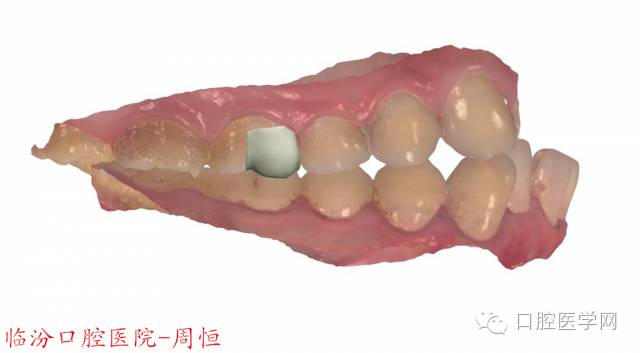

圖5 3D掃描咬頜觀

圖6 3D掃描頜面觀